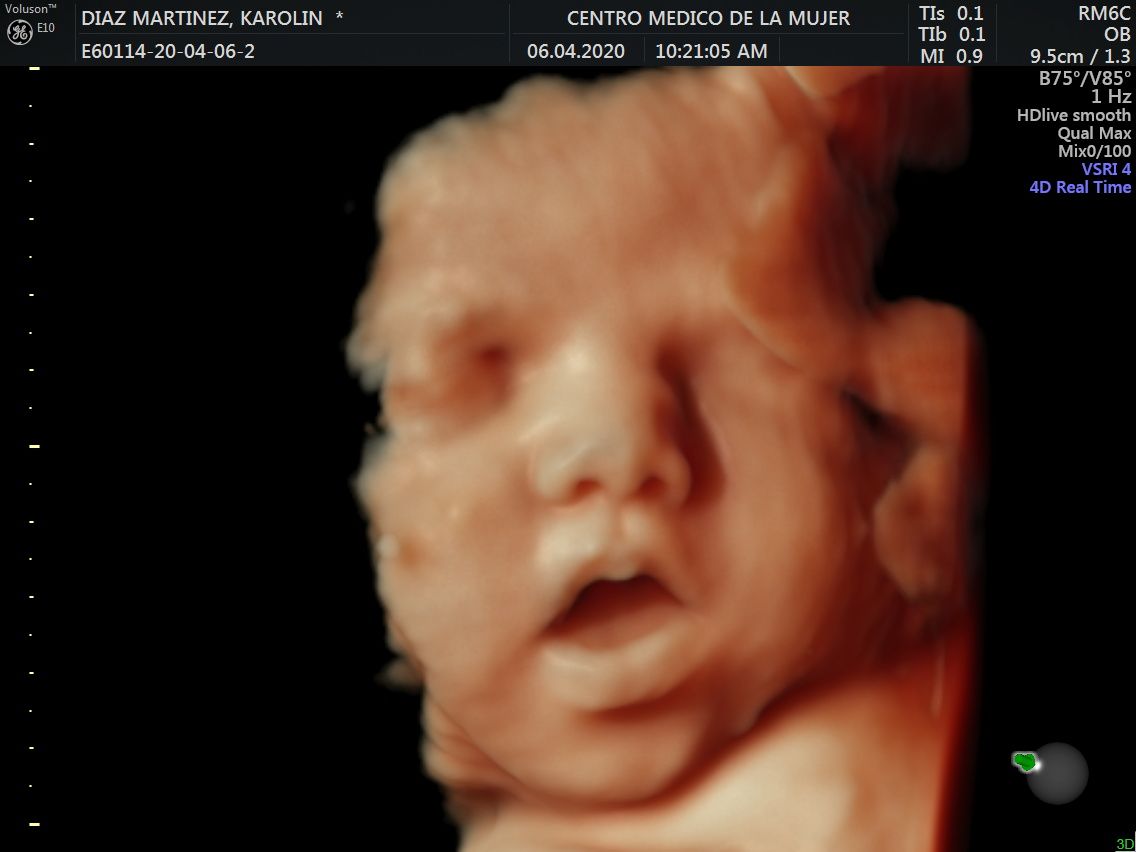

Fotos y videos

ECO Anatómico

Consiste en la evaluación especifica de cada organo y sistema del bebé con medidas detalladas de cada parte para evaluar su crecimiento proporcional.